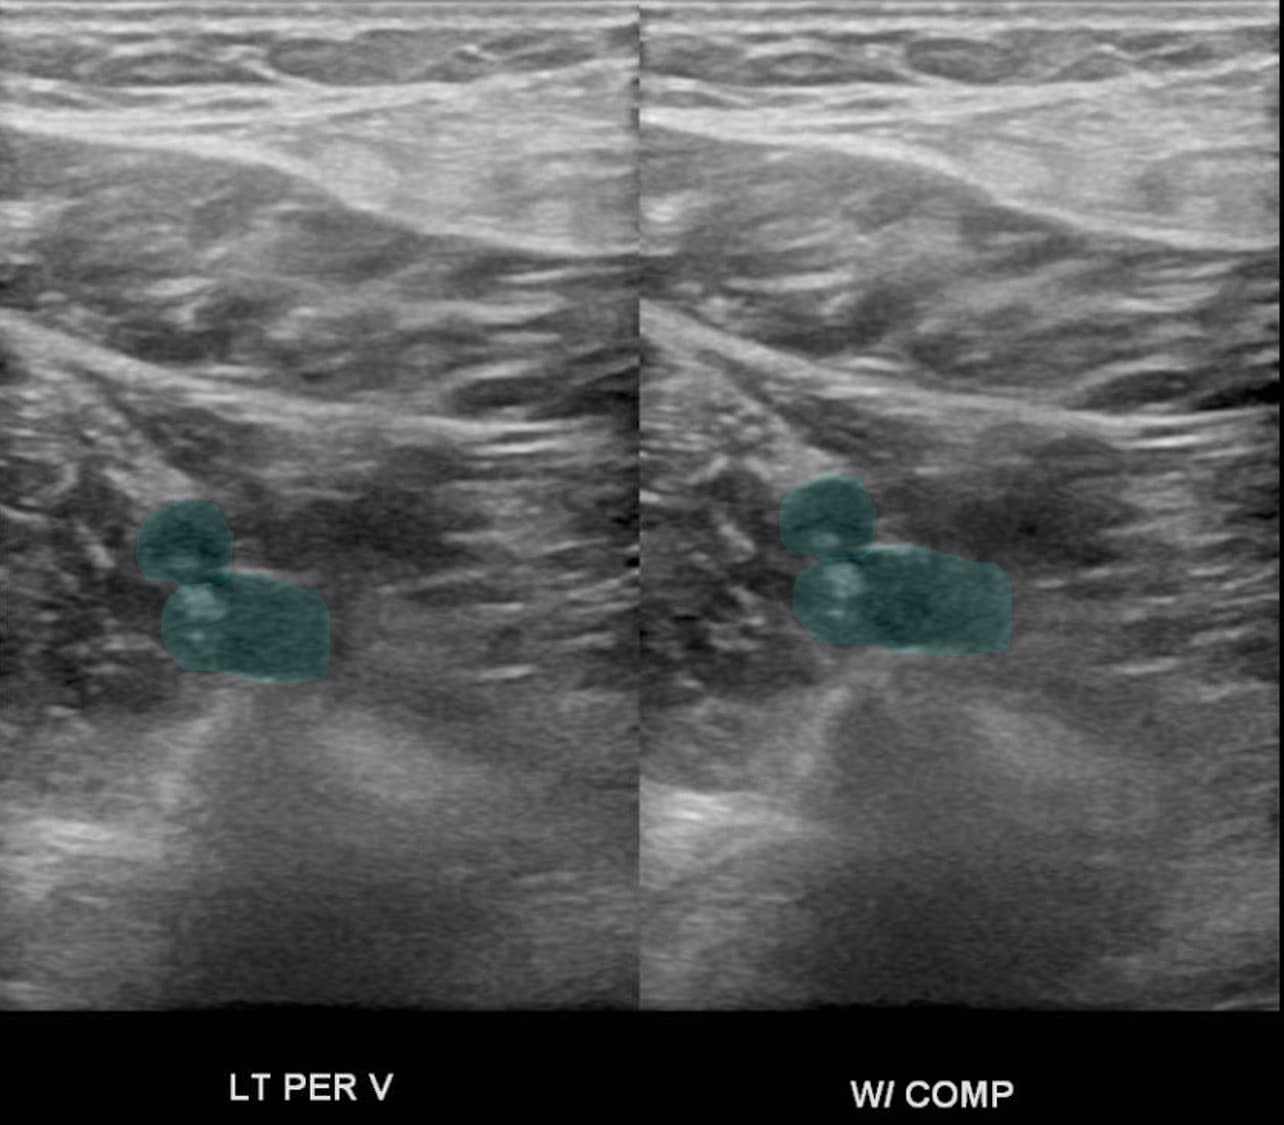

The diagnosis of calf vein thrombosis is established with duplex ultrasound utilizing the same principles that are used in proximal deep vein thrombi. A thrombus is diagnosed if there is lack of compression and/or lack of augmentation of flow. Also if there is no flow in the vein it may suggest a thrombosis. Some vascular laboratories do not perform calf ultrasound routinely, while others do. It is a matter of debate whether or not calf duplex ultrasonography is an accurate method to detect thrombi, however it has been published that a high standard laboratory can establish a low rate of clinically significant missed diagnoses.

An interesting fact is that calf vein thrombosis usually occurs in the gastrocnemius or soleus muscle veins or in the posterior tibial or peroneal veins. It rarely occurs in the anterior tibial veins. Duplex ultrasound which cannot visualize the anterior tibial vein appropriately is actually quite useful for the culprit veins outlined.